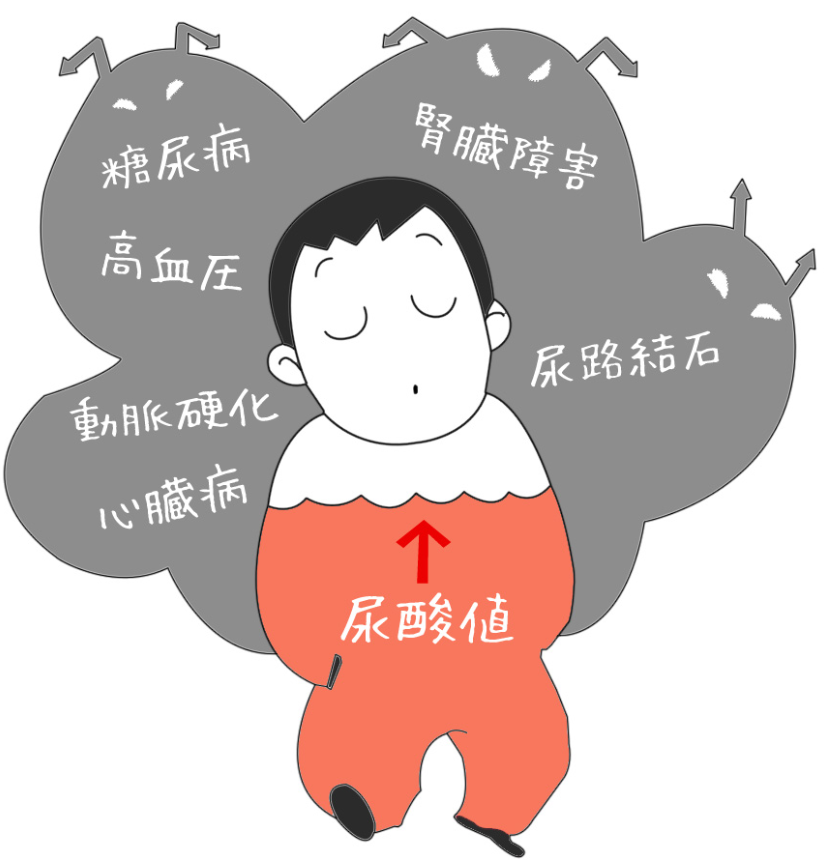

症状が進行すると、高尿酸血症に伴う臓器障害(尿路結石、痛風腎)なども生じてしまいます。

ビールやたらこ以外にはコーヒー、野菜類、海藻類、きのこ類、大豆製品と乳製品なども過剰に摂取すると、痛風につながることになります。

食べたいものを何でも大量に食べてしまうと人体は蝕まれていきます。

医師のアドバイスをフォローし、栄養バランスをよく考えながら健康的な食生活を送り、発症のリスクを回避することが大事です。